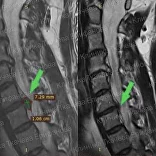

* Резорбция — процесс уменьшения грыжи диска за счет естественных физиологических способностей организма. Это основа эффективного лечения грыжи и альтернатива операции.

Метод модулируемой резорбции позволяет ускорить этот процесс, взять боль под контроль и улучшить качество жизни.